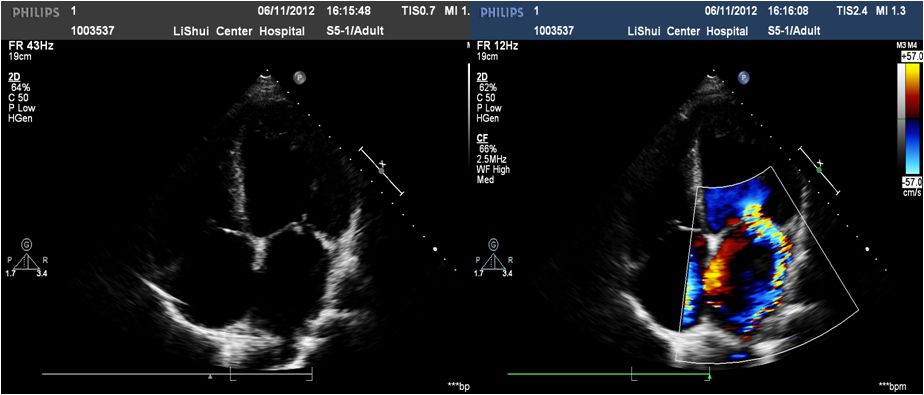

➤ 全心扩大(左房内径48mm,左室内径(d)75mm,(s)62mm)

➤ LVEF36%,肺动脉压80mmHg

➤ 二尖瓣前叶收缩期突向左房,二尖瓣收缩期见中重度关闭不全

➤ 室间隔厚11mm,左室后壁厚11mm